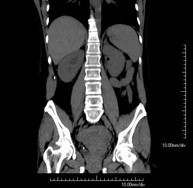

- TC Abdominopélvico

Prueba diagnóstica que consiste en obtener imágenes bi y tridimensionales del abdomen y de la pelvis de alta definición anatómica (estructuras óseas, estructuras vasculares, hígado, páncreas, vesícula biliar, riñones, glándulas suprarrenales, bazo, intestino delgado y grueso, vejiga, útero y ovarios, próstata y vesículas seminales, uréteres, etc.) mediante el empleo de un equipo de TC (Tomografía Computarizada). La mayoría de estudios requieren el empleo de contraste yodado.